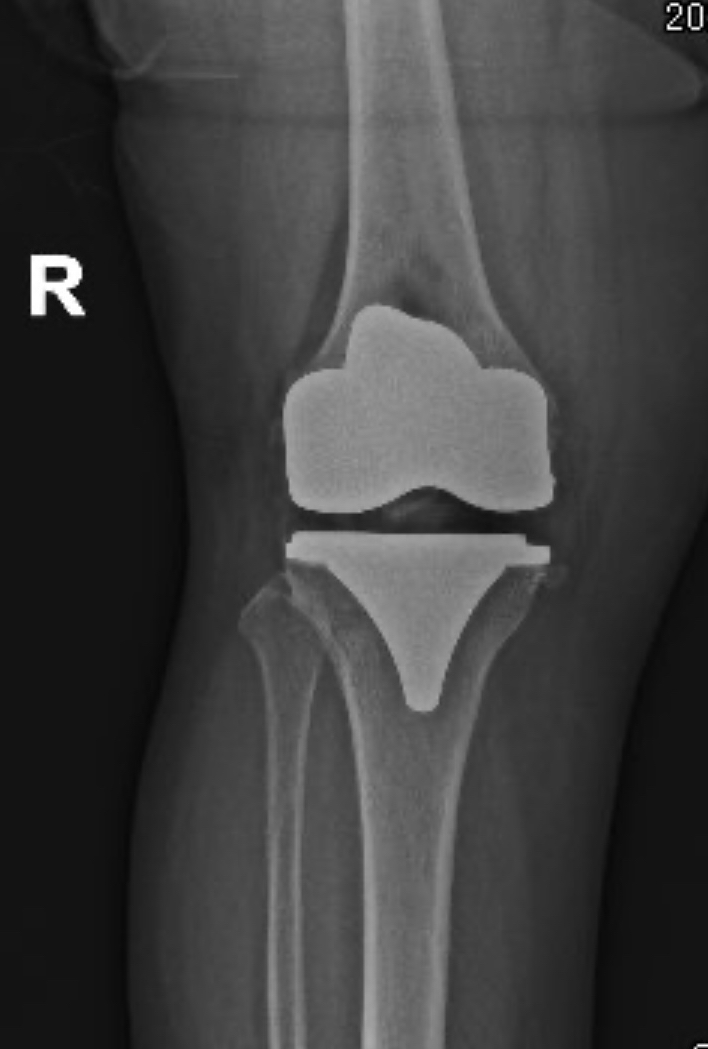

¿En qué consiste la cirugía de prótesis total de rodilla?

La prótesis total de rodilla es un procedimiento en el que se reemplazan las superficies dañadas de la articulación por componentes metálicos y de polietileno de alta durabilidad.

La cirugía elimina el desgaste causado por artrosis avanzada y permite recuperar movilidad y aliviar el dolor.

Se retira el cartílago y hueso deteriorado.

Se colocan componentes que recrean la forma natural de la rodilla.

Se equilibran los ligamentos para brindar estabilidad y movimiento fluido.